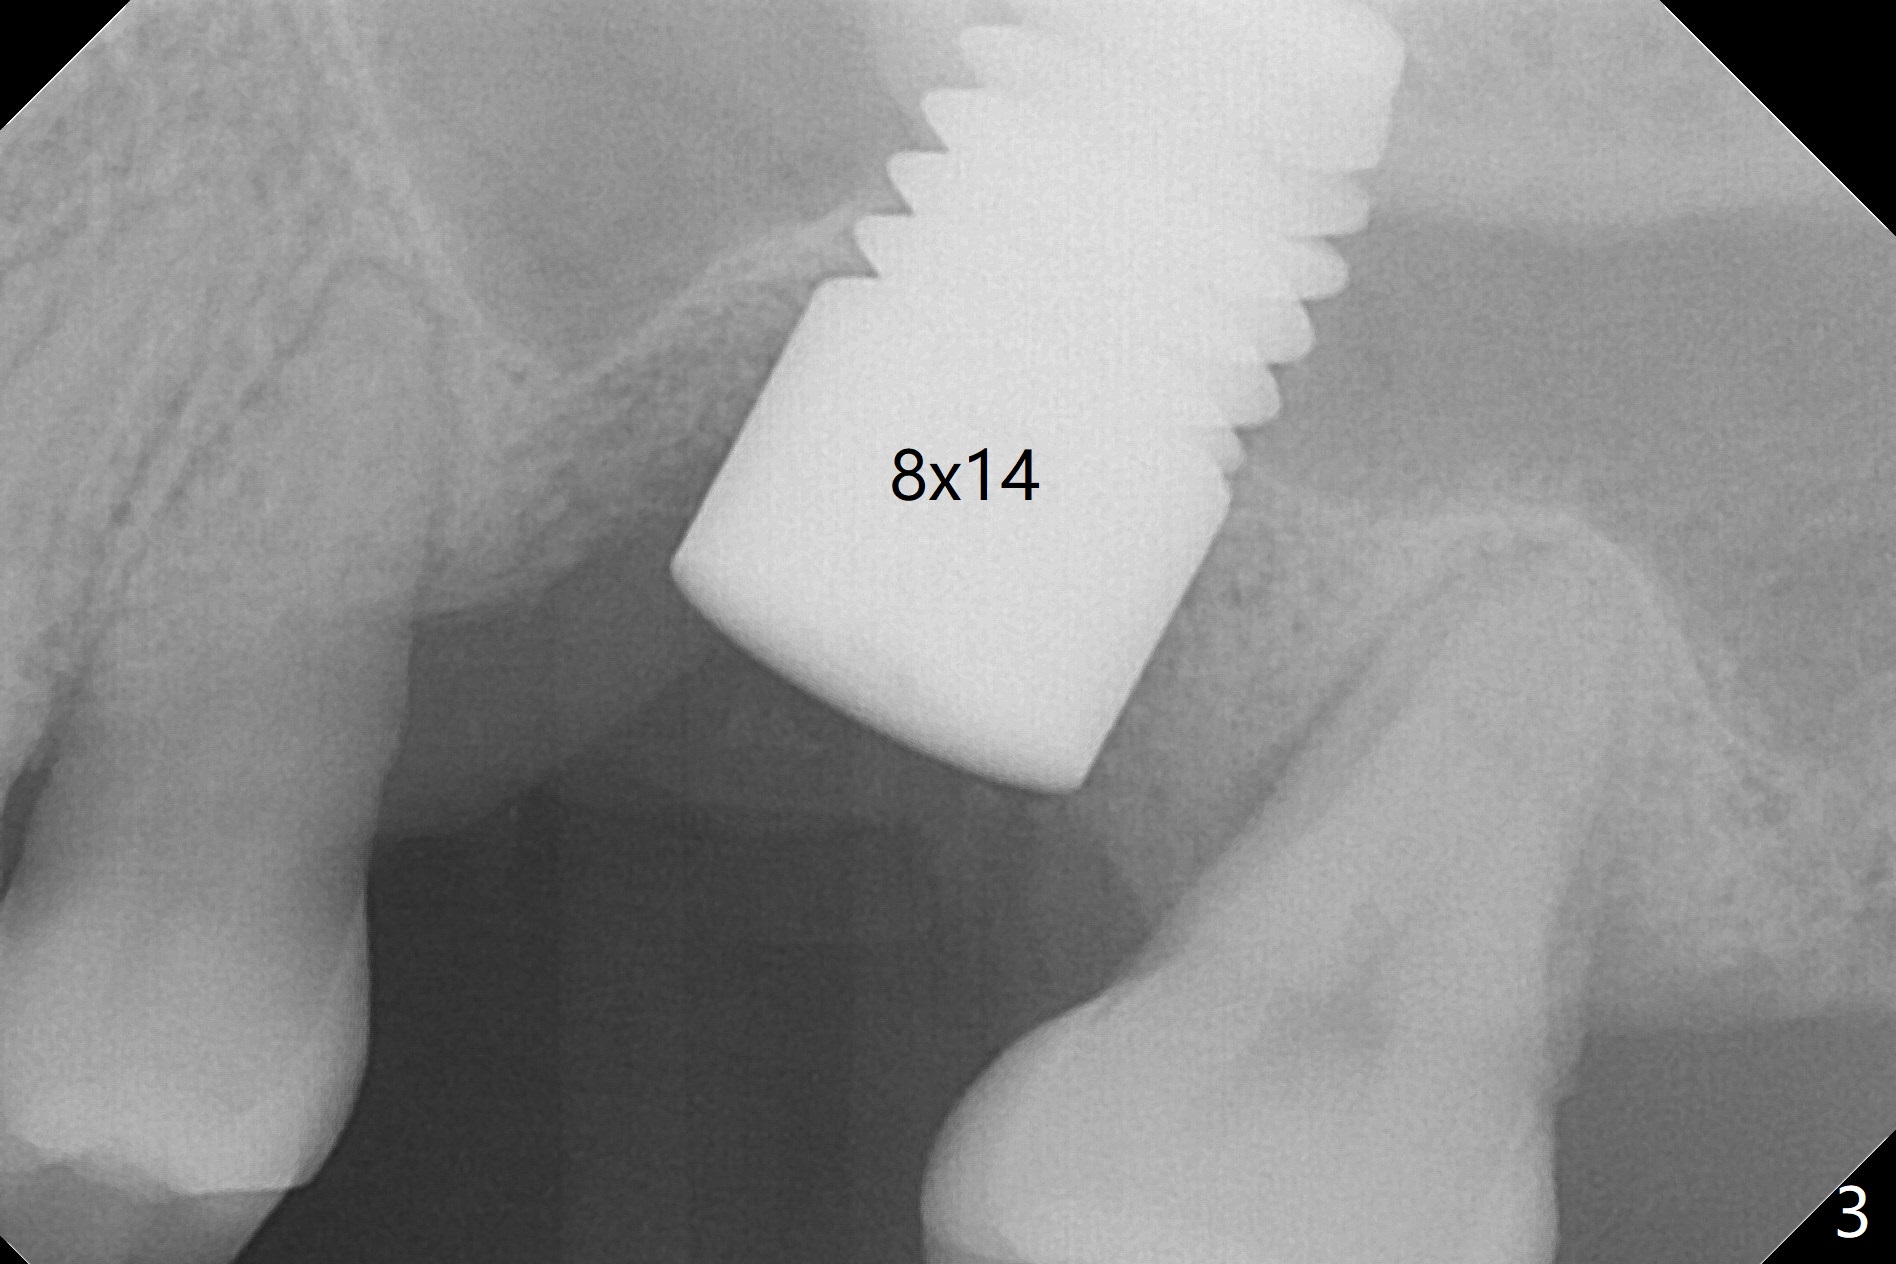

Three months post cementation, the implant at #14 is found loose (Fig.1: 6.5x11 mm) and removed. After removal of minimal granulation tissue, normal saline disappears into the apical end of osteotomy. In fact there is no bone apically, although the sinus membrane is intact. After try in of various taps (tapered and cylindrical, bone- and tissue-level), a 8x14 mm dummy implant is placed (Fig.2), followed by Osteogen plug and the same sized definitive implant, which has to be placed deeper to obtain ~ 45 Ncm (Fig.3). There is minimal thread engagement. If the implant fails, place 2 layers of PRF membrane apically, bone graft and 1 layer of PRF coronally for ridge preservation. A healing abutment will be placed to expose the coronal end of the implant ~ 4 months postop. The tissue-level implant remains subgingival 4.5 months postop (Fig.4). A 8 mm healing cuff cannot be placed even after laser gingivectomy. The implant is 2 mm subcrestal mesially. Torque wrench cannot reverse the implant at 60 Ncm. The implant is later reversed with Tatum wrench until it is turned with the torque wrench at 30 Ncm. The implant remains stable, while the healing cuff with Triple Antibiotic Ointment is placed. The healing cuff is stable 2 weeks later (Fig.5 C). With progressive loading for a month, a crown is cemented 9 months postop. There appears no bone loss 2.5 months post cementation (11 months postop, Fig.6). Return to Upper Molar Immediate Implant, Armaments, IBS #3 Xin Wei, DDS, PhD, MS 1st edition 04/30/2018, last revision 04/14/2019